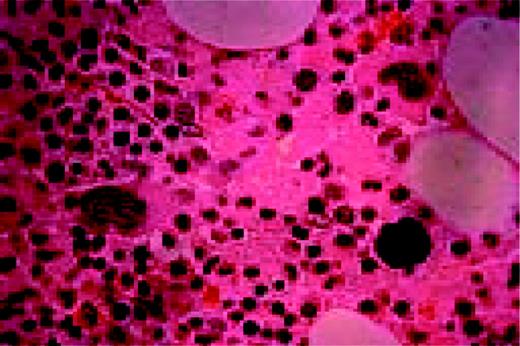

Slide L53

Hodgkin's disease associated with AIDS, bone marrow biopsy, H&E. Total replacement of normal bone marrow by an abnormal infiltrate including two Reed-Sternberg cells (top right).FIG53